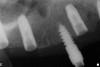

The patient was scanned with a cone beam CT scan while wearing a radiopaque scanning appliance based on her new treatment denture. Horizontal bone augmentation was confirmed radiographically, and both grafted sinuses resulted in satisfactory bone quantity for implant placement. Vertical augmentation was not attempted because of the patient’s unwillingness to forego her removable prosthesis for any period of time. Therefore, shorter implants were treatment-planned, resulting in the placement of eight implants, rather than fewer—such as six—implants, to support a full-arch fixed prosthesis. Because adequate bone and keratinized mucosa were present, a flapless, computer-guided implant insertion was performed (Figure 18). After removal of the surgical guide, placement of all eight implants could be inspected (Figure 19). Post-placement periapical radiographs are shown in Figure 20 and Figure 21.